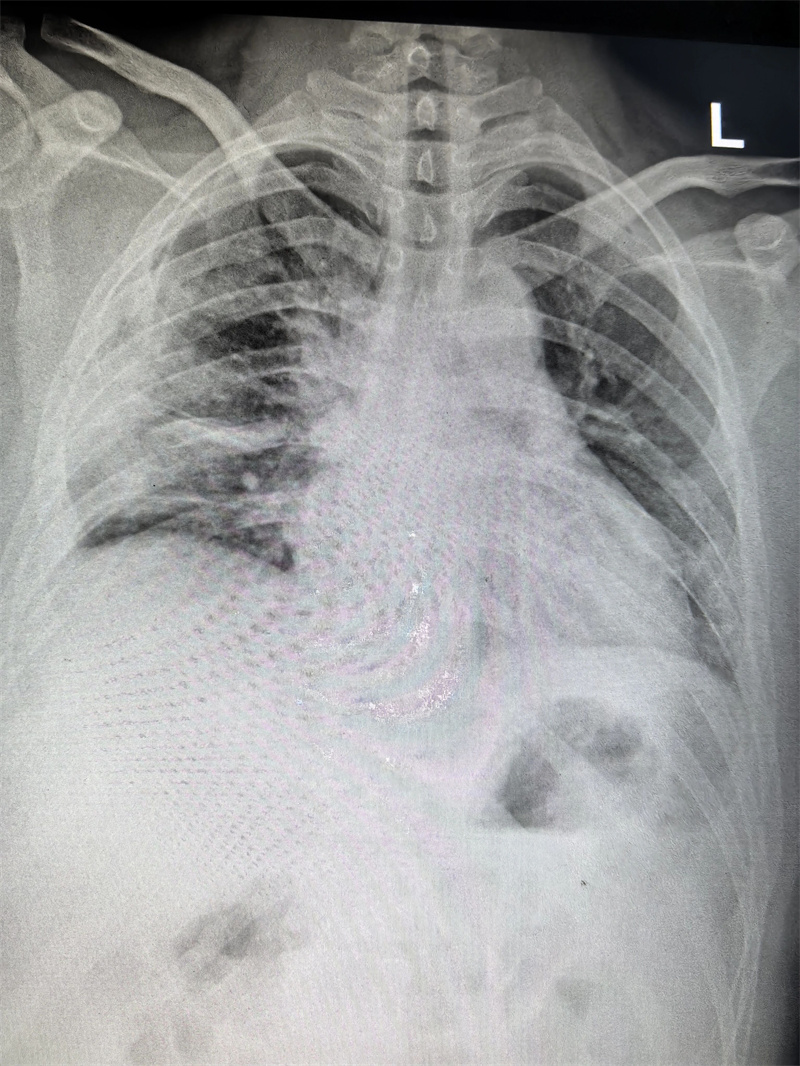

四个月前,23岁的小雨(化名)因胸闷前往医院就诊,CT检查结果显示右侧胸腔靠上位置出现包裹性脓胸,并进行穿刺检查,最终确诊为结核性包裹性脓胸,这个消息让小雨和家人陷入了深深的焦虑之中。

经过3个小时的紧张操作,包裹的脓肿被完整剥除,病灶彻底清除。术后切开脓肿,其内可见脓液,干酪物和坏死肉芽组织。

小雨的手术切口很小,大约只有4厘米,出血量也仅100ml,这对小雨的愈后起到了很好的作用。术后,小雨在医护人员的精心照料下恢复得很快,于10月24日顺利出院。

与传统开胸手术相比,胸腔镜下治疗结核性包裹性脓胸具有显著优势,出血少、伤口小、恢复快、痛苦少,患者能更早下地活动,住院时间明显缩短,经济压力也随之降低。

更重要的是,这种微创操作大大减少了污染物污染的可能性,降低了胸腔感染的风险,为患者带来了更优质、高效的治疗体验。